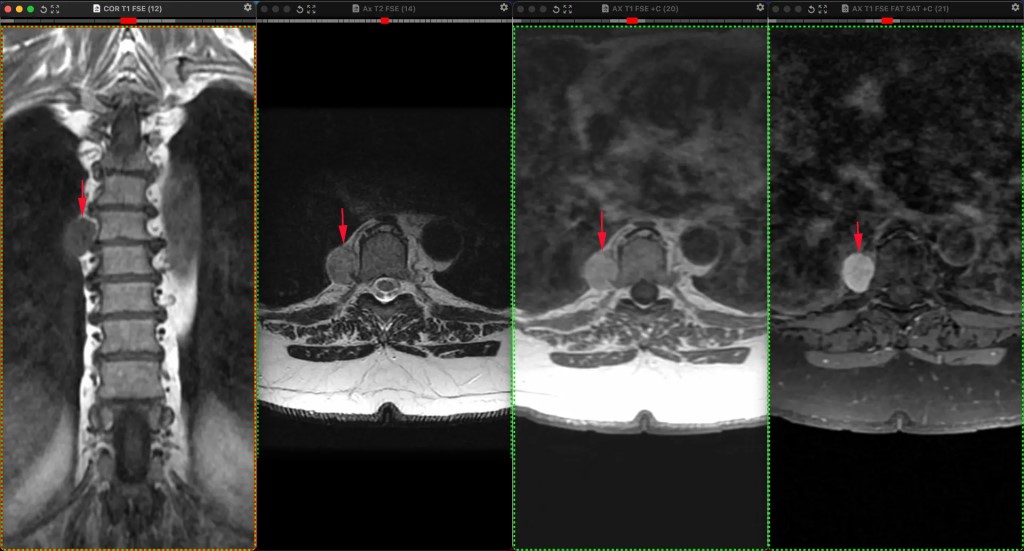

Фото Небезосновательно предполагаемая шваннома заднего средостение у женщины 54 лет, обследованной не по её поводу. Бессимптомная, как и почти всегда. Опухоли нервной системы чаще всего встречаются среди первичных новообразований средостения. Львиная доля их — доброкачественные. Шванномы — самые частые нейрогенный  опухоли в грудной клетке, которые развиваются из шванновских клеток периферических нервов (причём, любых, вплоть до самых мелких и необязательно спинномозговых) и часто сидят в заднем средостении. Обнаруживаются почти всегда случайно при проведении различных методов визуализации.  Интраторакальная шваннома чаще всего расположена в заднем средостении. Это -  медленно растущая доброкачественная опухоль с низкой вероятностью стать злокачественной. В крайне редких случаях злокачественной трансформации могут встречаться плеоморфные веретенообразные клетки и некротические и геморрагические изменения. Как и в данном случае, опухоль обнаруживается случайно при визуализации: эхокардиография, гастроэндоскопия, КТ или МРТ. Симптомы в подавляющем большинстве случаев, отсутствуют, но могут появиться, если опухоль начнет давить на окружающие органы.